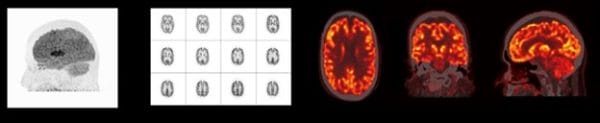

NEUROLOGY, neurology imaging workflows benefit from Biograph mCT’ s precise delineation of cerebral anatomy with TOF and small, 4 x 4-mm elements—including 78-mm 3 volumetric resolution and a large 400 x 400 acquisition matrix.

All photographs and data are a courtesy of Siemens Healthcare GmbH.